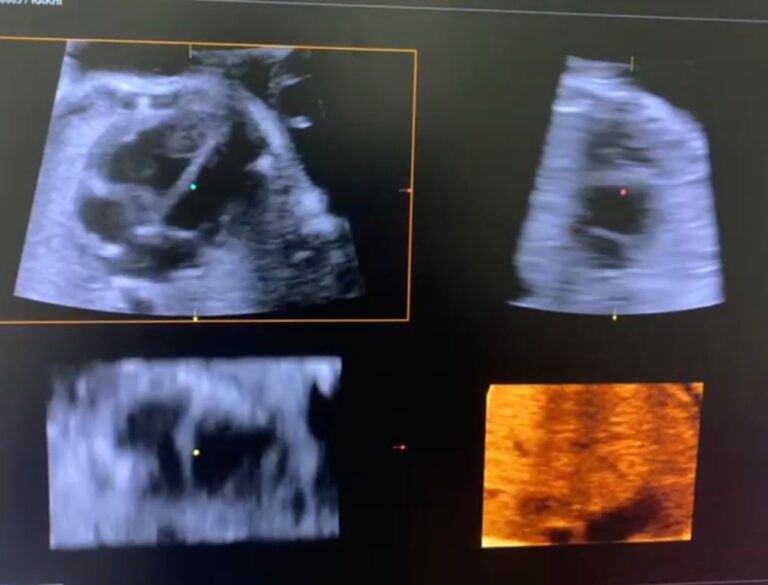

The fallopian tubes need to be healthy and open in order to become pregnant. Tests for tubal patency are fertility examinations that look for adhesions and obstructions in the fallopian tubes. It is estimated that between 15% and 20% of people experience infertility due to tubal abnormalities. Tubal examination is the first course of fertility investigation that Birla Fertility & IVF recommends. Tubal patency testing is advised for couples who have not been able to conceive after a year of consistent unprotected sexual activity and who do not have a clear cause for their infertility, as well as for couples who have previously failed IUI therapies. Tubal patency tests are especially recommended for women who have had surgery, endometriosis, or pelvic infections because these women are more likely to have obstructions.